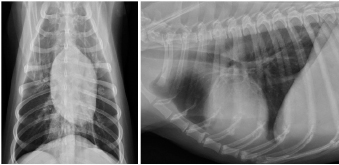

A 14-year-old spayed female Labrador retriever weighing 21.3 kg was referred to our hospital with a main complaint of chronic right-hind lameness. This patient had undergone surgery for right tibial fracture repair with implantation of bone plate and screws at a referral hospital 12 years ago. The patient showed no appetite, was not drinking, and was lethargic, with a body condition score of 1/5. The patient was unable to stand up on her own, her right hind limb was mostly weak, and she was unable to move independently using her left side. The patient’s state of consciousness was normal. On physical examination, her vital signs were normal (temperature: 38.1°C, pulse 104 beats/minutes with no heart murmur, respiratory rate with normal lung sounds: 32 beats/minutes). The mucous membrane showed a pale color because of severe anemia (packed cell volume 20.4%). In addition, the capillary refill time was delayed by <3 seconds, suggesting severe dehydration. The patient showed swelling and was warm to the touch from the right tibia to the femur, with a swollen right popliteal lymph node, which presented with a ruptured mass lesion approximately 7 × 10 cm in size. The thoracic radiograph was normal (Fig. 1). However, the right hind limb radiograph showed an osteolytic lesion accompanying the ruptured implant and loosening of the plate and screws, with surrounding soft tissue swelling (Fig. 2). Fine needle aspiration from this site suggested OSA (data not shown). Although we could not perform angiographic computed tomography because of the owner’s dissent, we performed amputation from the hip joint on the same day. Gross morphology showed severe inflammation surrounding soft tissues, the rupture of the stainless-steel bone plate, and we noted a non-medical band at the right tibia (Fig. 3). The patient was formally diagnosed with OSA after histopathological examinations (Fig. 4). After 24 hours hospitalization, we administered ampicillin potassium (20 mg/kg, BID) intravenously and prednisolone (0.5 mg/kg, SID) subcutaneously for postoperative care. Also, 24 hours continuous rate infusion of fentanyl (5 μg/kg/minutes) in lactated Ringer’s solution was used for analgesia. The patient was discharged to the owner the day after surgery for home care. The owner refused postoperative radiation therapy and chemotherapy. Unfortunately, this patient died 1 month after amputation.

Fig. 1. Thoracic radiographs.

No metastasis was observed.

Fig. 2. Limb radiographs. The right tibia showed an osteolytic lesion with rupture of orthopedic plate, loosening of screws, and also soft tissue swelling.